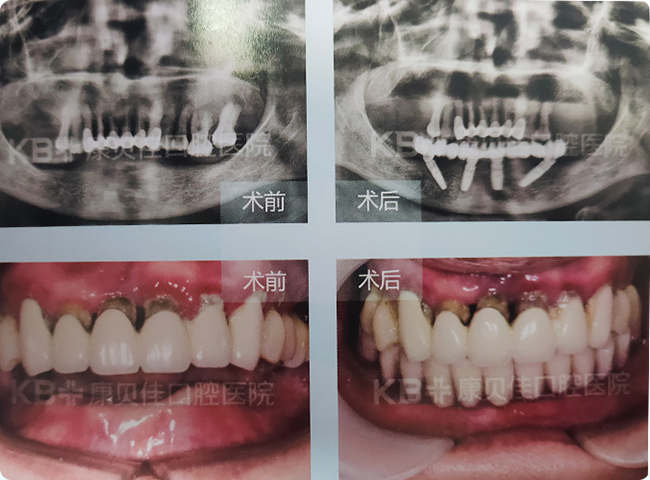

胡女士 65岁

50为多岁因牙周病导致下半口牙陆续脱落,戴过8年活动假牙,但感觉不舒服。为提高生活质量想到了种植牙,去过多家口腔机构咨询,听朋友说康贝佳技术好、后期跟踪服务也好,经过对比和实地考察后选择康贝佳,采用种植4颗即刻恢复技术种好了下半口牙,当天就能啃苹果。

治疗方案:

下颌种植4颗恢复半口